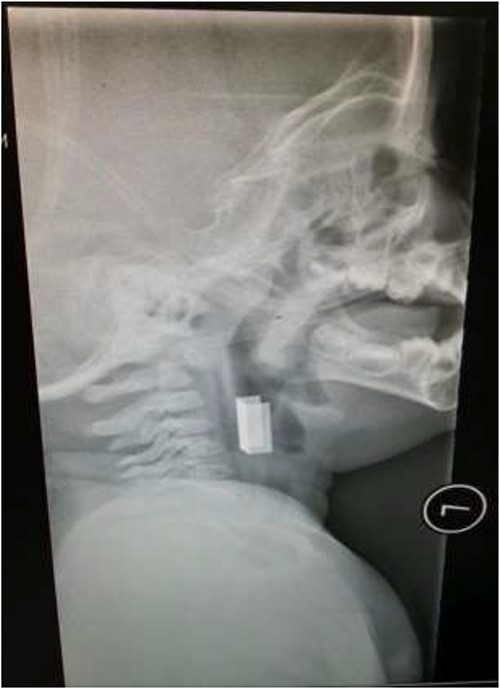

The first case is of a 7-year-old child presenting with a history of barbed wire inhalation. X-ray imaging of his neck and chest showed a radio-opaque object visible in the upper airway with sharp edges (Figs 1 and 2). Due to the position of the foreign body, endotracheal intubation was not feasible. A trial of apnoeic oxygenation using high-flow nasal oxygenation was used as an alternative, and this allowed for an unobstructed view of the larynx, facilitating the safe removal of the foreign body (Fig. 3).

AP chest radiograph showing the sharp-edged radio-opaque object.